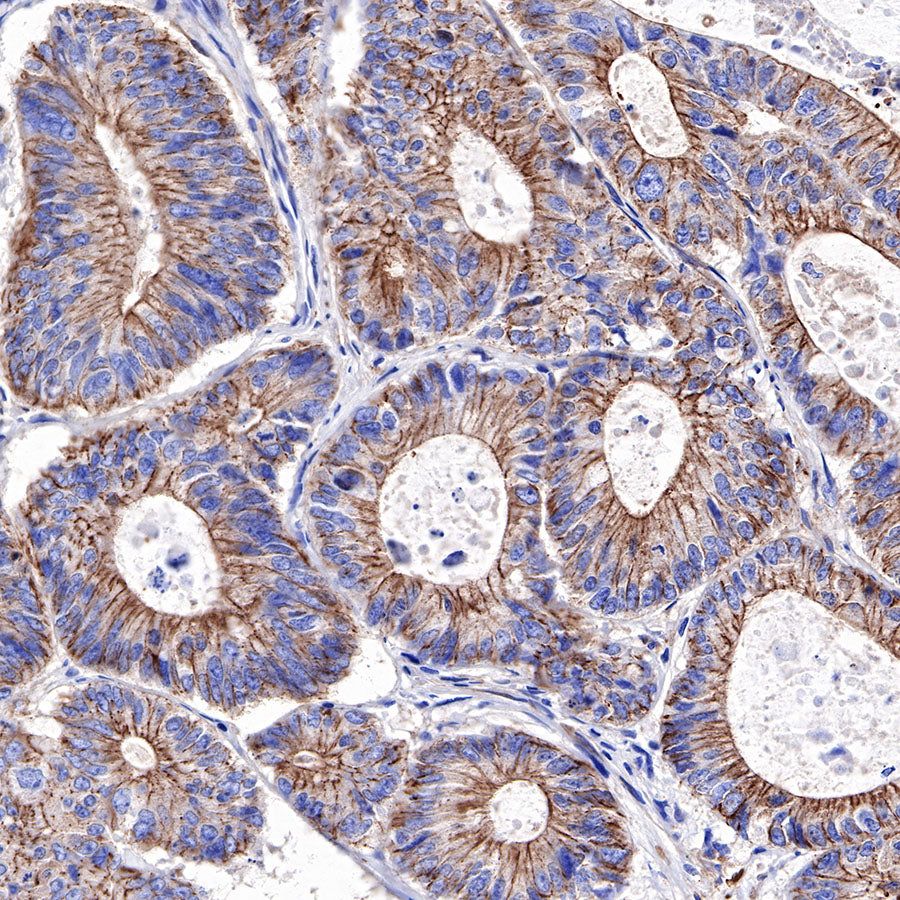

IHC shows positive staining in paraffin-embedded human colon cancer. Anti-α-Actinin-1 antibody was used at 1/2000 dilution, followed by a HRP Polymer for Mouse & Rabbit IgG (ready to use). Counterstained with hematoxylin. Heat mediated antigen retrieval with Tris/EDTA buffer pH9.0 was performed before commencing with IHC staining protocol.